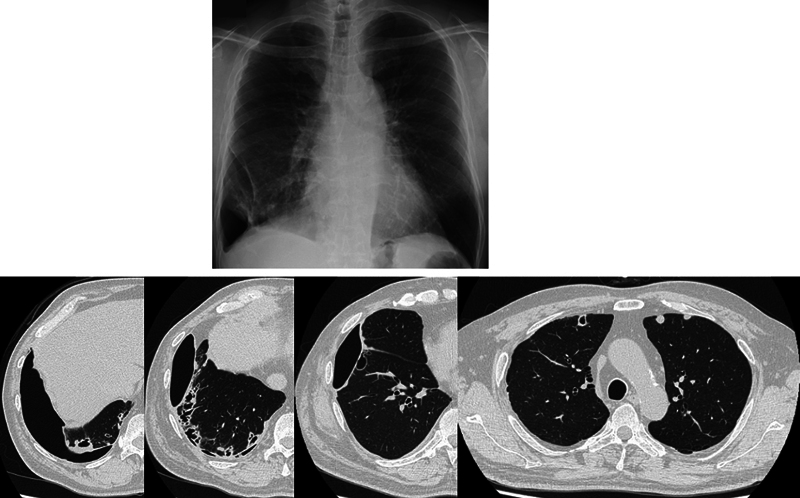

Background  No consensus exists regarding surgical intervention for rheumatoid nodule-related pneumothorax. Clinical policy decisions rely on individual clinicians' experience and are usually intractable. Case Description  A 50-year-old man with a difficult-to-treat rheumatoid arthritis-related pneumothorax was successfully treated with pedicle omentoplasty without recurrence at approximately 2 years posttreatment. To the best of our knowledge, this is the first report of a patient where pneumothorax did not recur due to firm adhesions despite fluctuating postoperative rheumatoid nodules, as captured by regular computed tomography imaging follow-ups. Conclusion  Pedicled omentoplasty is effective for rheumatoid nodule-related pneumothorax as it reduces pneumothorax recurrence.